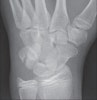

Avulsion chip fracture는 lateral, oblique view에서 잘 보입니다.

X-ray : 삼각골 골절(Triquetrum fracture)